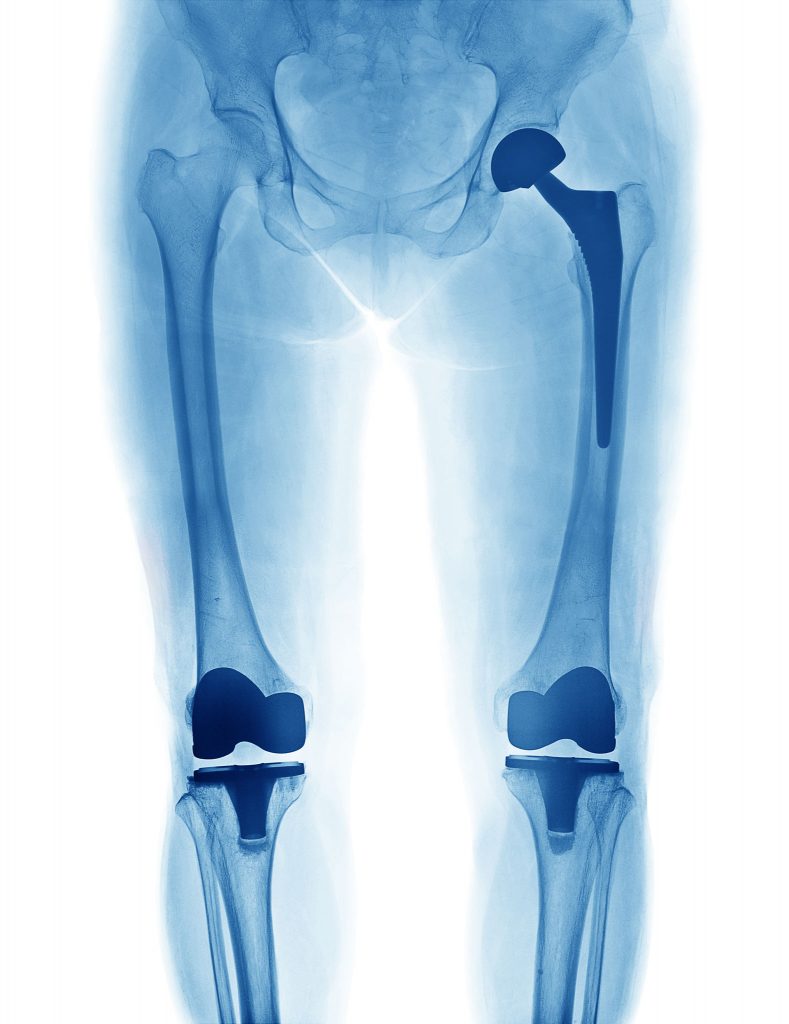

Knee

Healthy knees are essential for staying active and are especially prone to injuries due to constant pressure and activities – from the mundane to strenuous. No matter the issue, Phoebe’s Orthopaedics & Sports Medicine team treats a full range of knee conditions to reduce pain and restore mobility, turning to advanced surgical solutions only when necessary. Sports, hobbies, playing with grandchildren and even just kneeling for household chores are all the things that we want to get you back to faster. With the largest orthopaedic team in Southwest Georgia, Phoebe provides the experience, technology, and personalized care needed so you can get back to your routine comfortably and safely.

- Knee Replacement (Total or Partial)

Hip

Hip pain can limit your movement and quality of life. The hips play a crucial role in the body’s mobility and stability, and can significantly degenerate if hip disorders are left untreated. Hip pain is debilitating, coupled with difficulty moving it can make everyday tasks feel impossible. Our specialists treat conditions ranging from arthritis and joint degeneration to injuries requiring hip arthroscopy or total hip replacement — all performed with a full range of orthopaedic surgical services. These advanced treatments can get you moving faster and better than ever. With the largest orthopaedic team in Southwest Georgia, Phoebe provides the experience, technology, and personalized care needed to get you back to the things you love.

- Total replacement

Robotic Surgery

Phoebe Sumter Medical Center (PSMC) has expanded its robotic surgery capabilities by providing total knee and hip replacements using Mako 4 SmartRobotics™. This innovative technology expands access to advanced orthopaedic care for patients in and around Sumter County and transforms the way total knee and hip replacements are performed by assisting surgeons, leading to a more personalized surgical experience.

Blue Distinction Centers for Knee and Hip Replacement by Blue Cross Blue Shield Association

Our facility has been recognized by Blue Cross Blue Shield as a Blue Distinction Center for Knee and Hip Replacement — a designation awarded to hospitals that demonstrate high standards in joint replacement care. This recognition highlights our consistent performance in delivering safe, effective knee and hip replacement procedures with lower rates of complications and hospital readmissions. It also reflects our commitment to evidence-based practices that support stronger outcomes for patients.